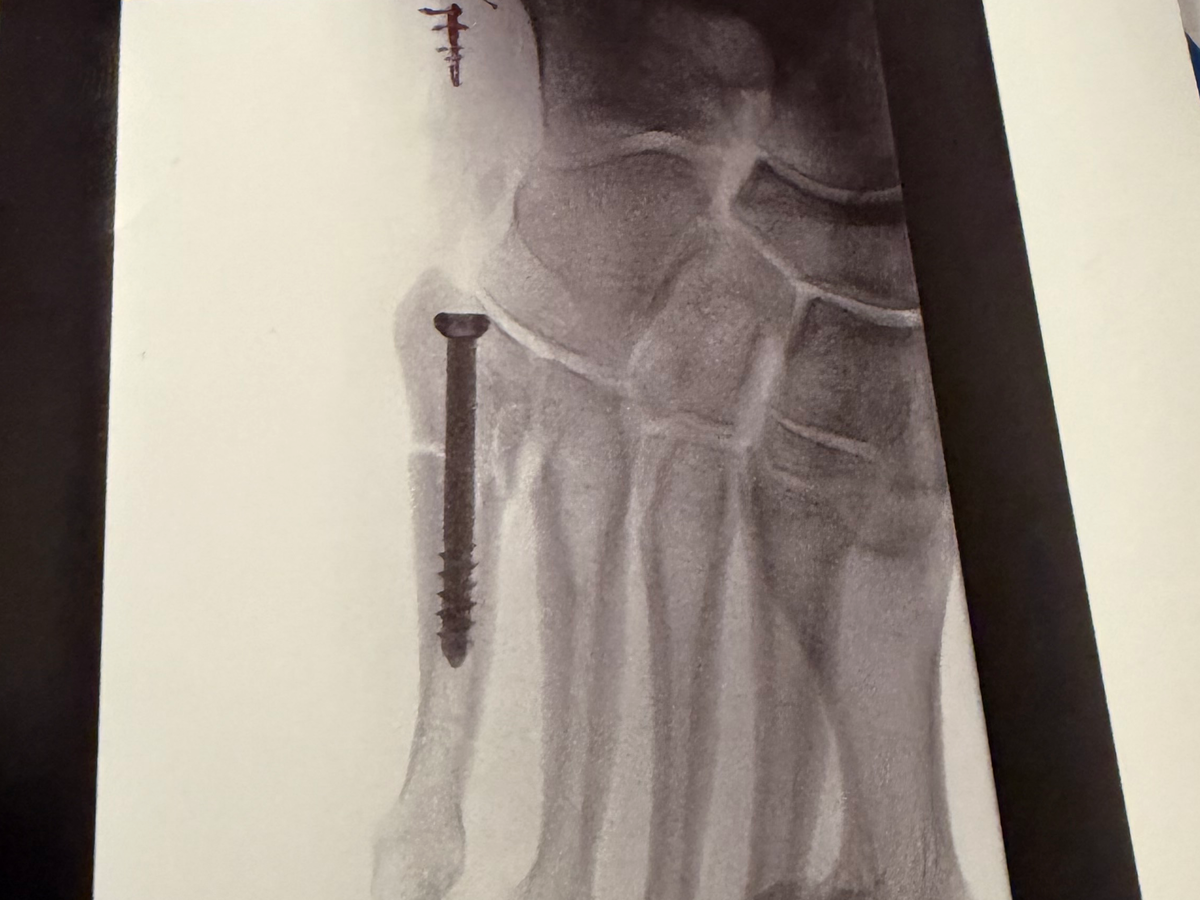

I recently took a trip down the stairs while trying to bring my sick roommate something. I missed the last step, twisted my ankle, and broke my foot. I have what’s known as a Jones Fracture and it needs surgery!